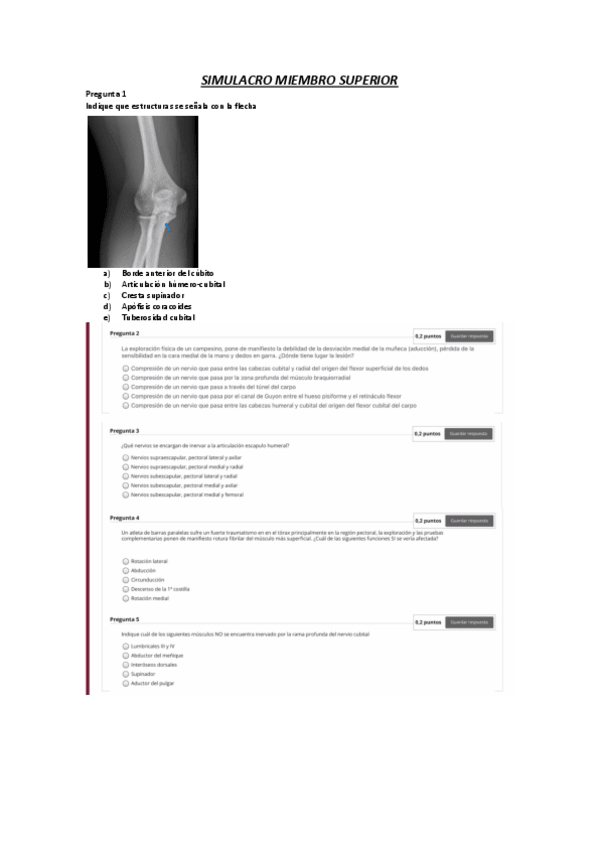

SIMULACRO-MMSS-2021-GRUPO-A.pdf

Pruebas miembro superior

ERROR SOLUCIÓN PREGUNTAS PRÁCTICAS. Pregunta 1 (sobre la escápula) --> a,e. Pregunta 7 (sobre la clavícula) --> a,b,d